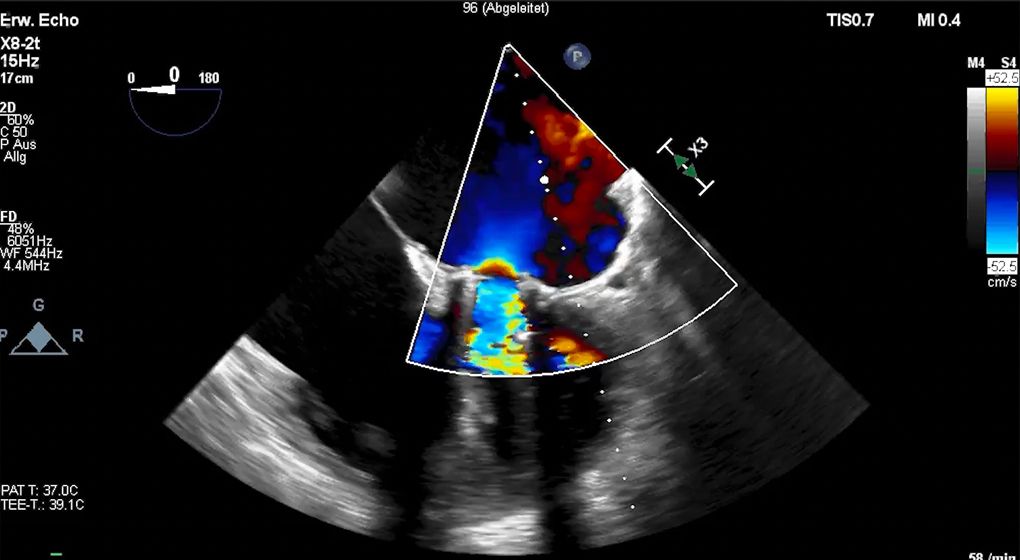

Im Laufe der Zeit können sich nach einem operativen Aortenklappen- oder Mitralklappen-Ersatz Undichtigkeiten im Bereich der Naht, neben der Herzklappe entwickeln.

Die sog. paravalvulären Lecks  können wir seit geraumer  Zeit mit einem Schirmchen-(Okkluder)-System  erfolgreich verschließen. Diese Therapie stellt insbesondere für Hochrisiko-Patienten eine tolle Alternative dar, da der Eingriff  über einen Leistenzugang durchgeführt werden kann. Während des Eingriffes wird der Patient aus einem kompetenten Herzteam, bestehend aus einem interventionellen Kardiologen, einem Echokardiographeur, Herzchirurgen und Anästhesisten, begleitet.